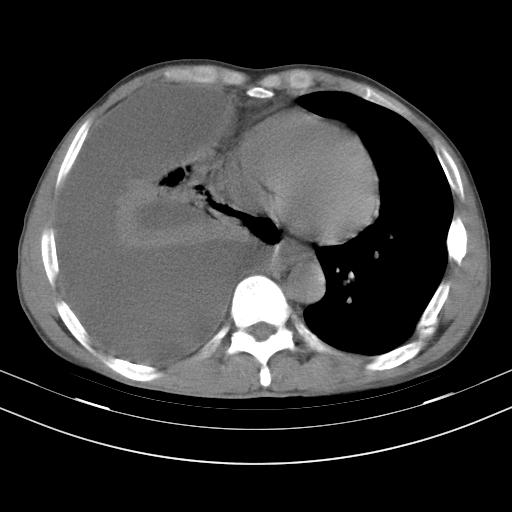

男性,44岁,结核病史多年。现胸闷气短,咳嗽,偶咳血。

右侧胸腔积液

右肺下叶不张

双肺多发结节影最分空洞形成考虑占位不除外结核

双肺陈旧性病变

1、右侧大量胸腔积液伴右肺压缩性膨胀不全,建议抽液治疗后复查 2、两肺继发性tb伴空洞形成。

1)两肺继发性肺结核伴空洞形成,左肺多发性结核球。2)右侧大量胸腔积液伴右肺部分膨胀不全。3)纵隔淋巴结肿大。

1,双肺多发结节 并空洞影改变, 左侧胸腔积液并部分包裹, 结合原病史首先考虑结核. 但也不除外其它.

2,左侧有一根肋骨陈旧性骨折? 建议追查 .

吉大一院胸水抽检结果:结核性胸水